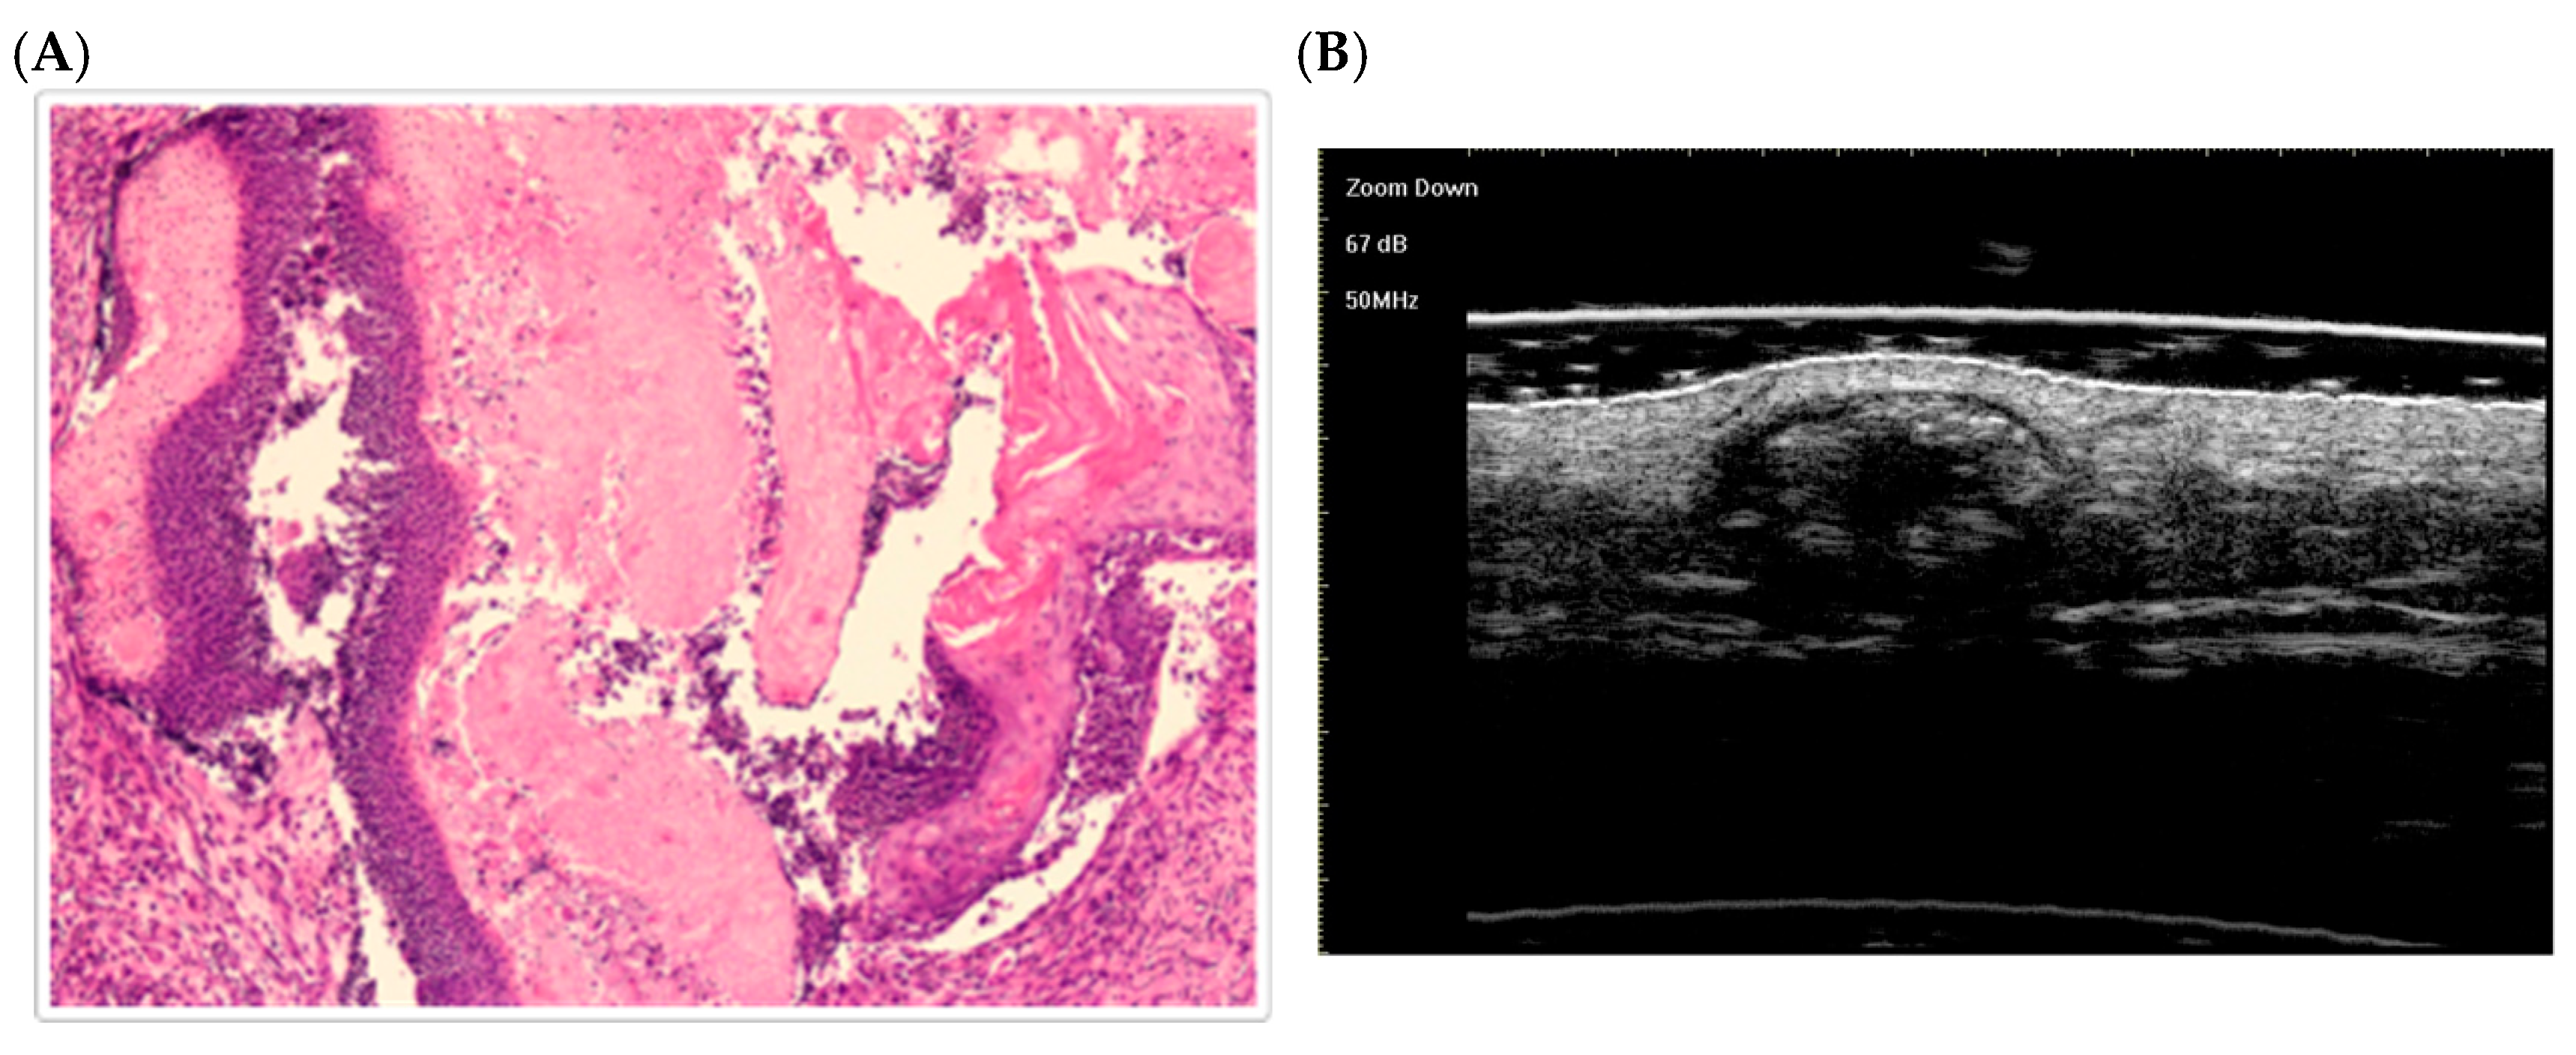

10. Pilomatricoma: Histological Morphological Stages

- In the early stage, the lesion appears as a small cyst with internal fissuring, filled with keratin and ghost (shadow) cells, and surrounded by a peripheral layer of basaloid cells.

- In the fully developed stage, larger eosinophilic keratin masses containing numerous shadow cells are surrounded by a mantle of active peripheral basaloid cells [58].

- The regressive stages are marked by loss of basaloid epithelium:

- In the early regressive stage, residual basaloid aggregates persist at the periphery, with central shadow cells, inflammatory infiltrate, and multinucleated giant cells.

- In the late regressive stage, the tumor becomes an amorphous keratinized mass (often calcified/ossified), with very few viable cellular elements [58].

- Li, L.; Xu, J.; Wang, S.; Yang, J. Ultra-High-Frequency Ultrasound in the Evaluation of Paediatric Pilomatricoma Based on the Histopathologic Classification. Front. Med. 2021, 8, 673861. [Google Scholar] [CrossRef]